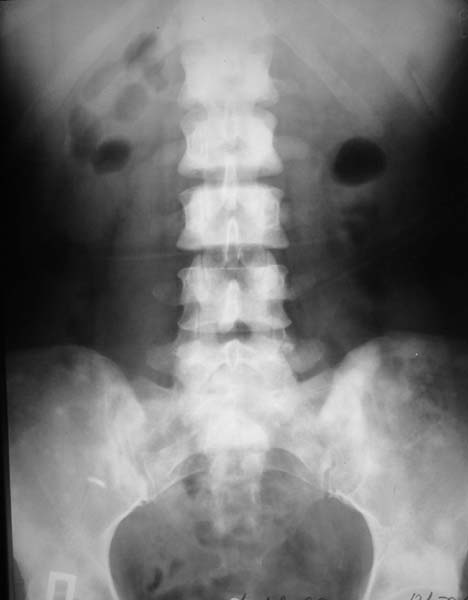

При МРТ (29.10.06) обнаружены диффузно-очаговые изменения в пояснично-крестцовом отделе позвоночника предположительно вторичного характера.

В октябре 2006 г. по поводу маточного кровотечения (менопауза 4 мес.) выполнено УЗИ - гиперплазия эндометрия, полипоз. Операция - удаление полипа, выскабливание полости матки. Цитологический анализ - пласты переходного климактерического эндометрия.Проведено комплексное исследование. В приложении: рентгенограммы и томограммы поясничного отдела позвоночника; радиологические исследованиямолочной железы, ЖКТ, почек, грудной клетки, анализы.УЗИ (18.12.06.) щитовидной железы, молочных желез - без патологии (умеренный фиброз по ходу млечных протоков).

Остеосцинтиграфия 4.12.06. - активный остеобластический процесс в поясничном, нижнегрудном отделах позвоночника, костях таза.Местными онкологами онко-процесс исключен. Фтизиатрический и онкогематологический диагнозы исключены.

Диагноз, исходя из сцинтиграфии, предположительно метастазирование без определения первичного очага. Я сделал бы КТ органов и костей таза. Следующим шагом желательно взять биопсию, возможно из крыла таза (будет проще) после четкой визуализации очагов на КТ...